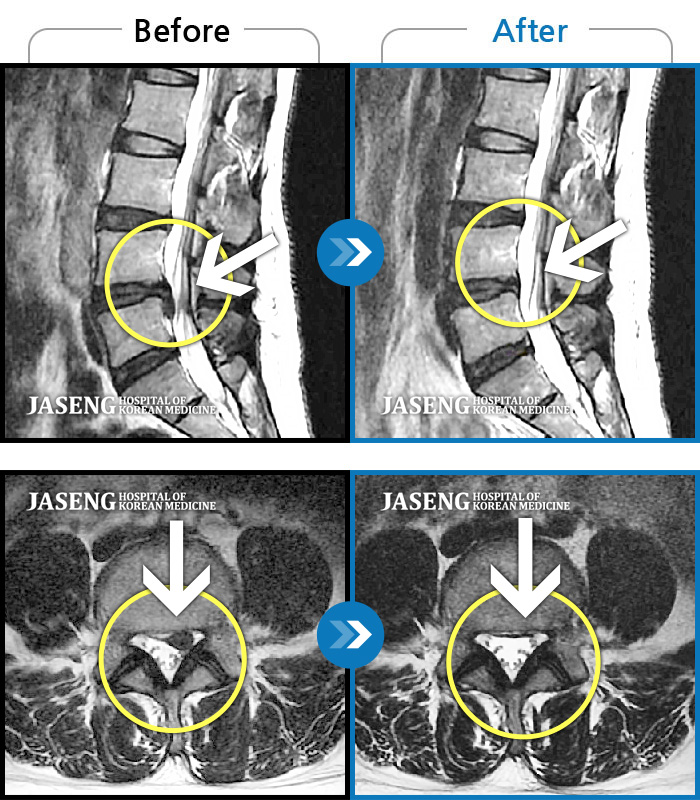

Before

After

환자에게 사전 동의를 받아 동일 조건에서 촬영되었습니다.

개인에 따라 치료 후 부작용이 발생할 수 있으니 의료진과 상담 후 치료를 진행하시기 바랍니다.

요추 4,5번 급성 허리디스크

허리디스크로 인한 다리 통증